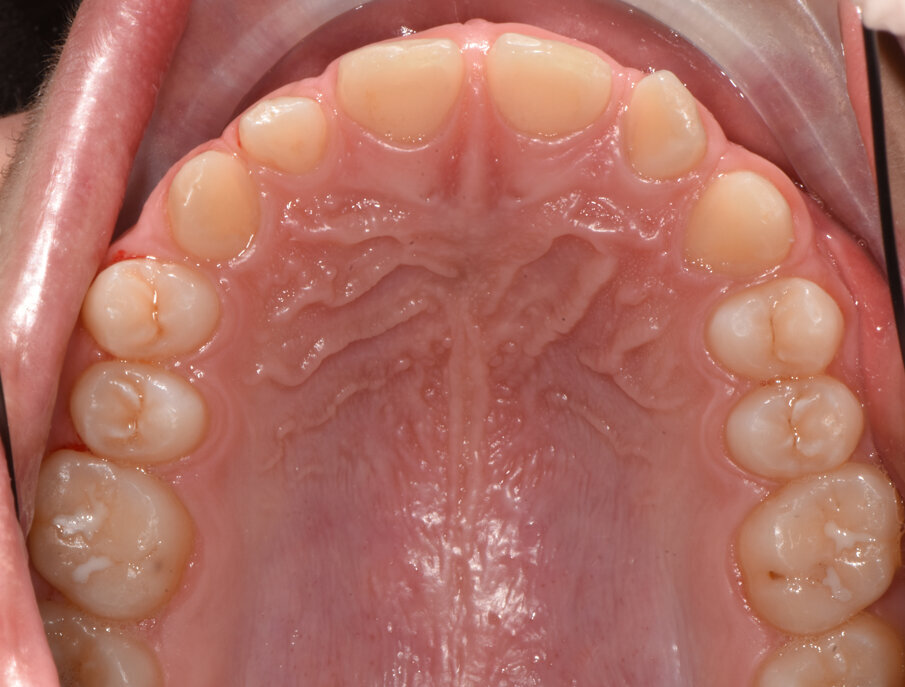

La piccola Sofia viene sottoposta a una prima visita ortodontica all’età di 8 anni, l’esame obiettivo (Figg. 1, 2) e l’ortopantomografia (Fig. 3) delle arcate dentarie evidenziano una mancanza di spazio per la corretta eruzione dei canini superiori (1.3-2.3).

Fig. 2_Vista occlusale iniziale.